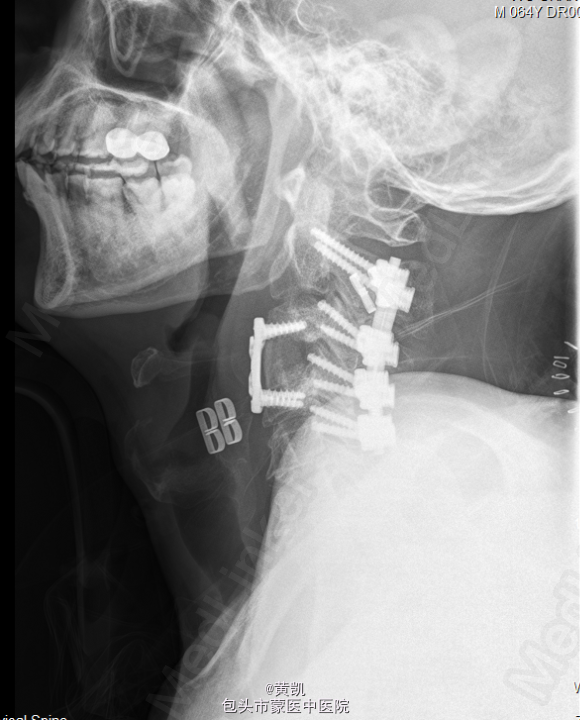

初步诊断:1.颈椎结核 2.胸椎结核 3.2型糖尿病.处理:行“颈椎前路结合病灶清除植骨融合内固定术+取髂骨植骨术+颈椎后路内固定术”。

手术顺利,术后恢复可,切口愈合佳,无明显渗出。目前一般情况可,生命体征平稳,切口愈合佳。